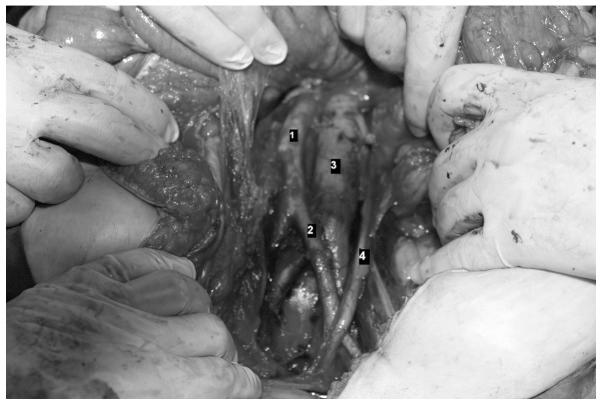

Situs inversus is a rare congenital anomaly in which the organs are transposed from their normal site to the opposite side of the body. To the best of our knowledge, this is the first study of staging laparotomy performed in a patient with endometrial carcinoma and situs inversus totalis (SIT). This study presents a patient with early endometrial carcinoma with SIT who underwent staging laparotomy. Total abdominal hysterectomy with bilateral salphingoophorectomy, omentectomy and pelvic para-aortic lymph node dissection was successfully performed without additional blood loss and time. The number of retrieved lymph nodes was 47. No abnormal course of blood vessels except for the right/left inversion was found. The postoperative course was favorable and the patient was discharged eight days after surgery.

内脏反位是一种罕见的先天性异常,其中器官从其正常位置转移到身体的另一侧。据我们所知,这是首例针对患有子宫内膜癌和完全性内脏反位(SIT)的患者进行分期剖腹手术的研究。本研究报告了一名患有早期子宫内膜癌合并SIT的患者接受了分期剖腹手术。成功实施了全腹子宫切除术、双侧输卵管卵巢切除术、大网膜切除术和盆腔及腹主动脉旁淋巴结清扫术,未出现额外失血且手术时间正常。获取的淋巴结数量为47个。除左右反位外,未发现血管走行异常。术后恢复顺利,患者术后8天出院。